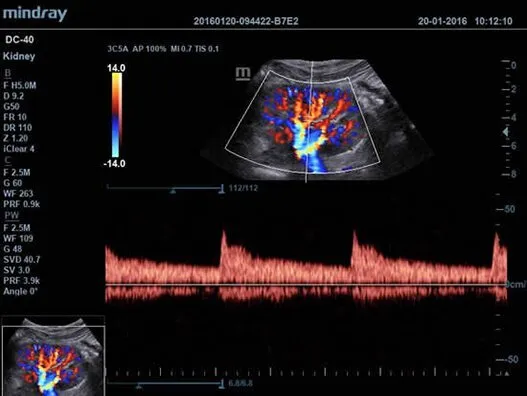

Клинические изображения

| 3C5A | Конвексный датчик для абдоминальных исследований, акушерства, гинекологии, урологии и сосудистых исследований |